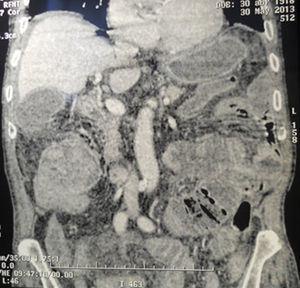

Al examen: lúcido y hemodinámica estable, anemia clínica. Abdomen: blando, depresible e indoloro, sin tumoraciones. TR: esfínter normotónico, no tumoraciones, materias sanguinolentas. Hb: 10,1 g/dl. Fibrocolonoscopia: lesión vegetante en ángulo derecho de colon, infranqueable al endoscopio. Biopsia: adenocarcinoma moderadamente diferenciado. Tomografía abdominal: intususcepción ileocólica en el ángulo derecho: clásica imagen de diana en corte transversal (fig. 1) e imagen en seudoriñón en corte longitudinal (figs. 2 y 3).

Debido al alto riesgo anestésico se realiza una derivación interna: íleo-transversa anastomosis latero-lateral. Seguimiento a 6 meses: transito digestivo normal. La intususcepción es una causa rara de obstrucción intestinal1, presente un 5% de los casos en los adultos2. La clínica es inespecífica, dada por: dolor abdominal, diarrea, náusea y vómitos. Según la localización se clasifican en: entérica, ileocólica (la mayoría), ileocecal o colónica. La etiología neoplásica —oficia como cabeza de invaginación— responsable de la intususcepción es infrecuente. El diagnóstico se realizó por el hallazgo tomográfico patognomónico, como es la imagen en «diana» en el corte transversal y de «salchicha o seudoriñón» en el corte longitudinal y anteroposterior3.